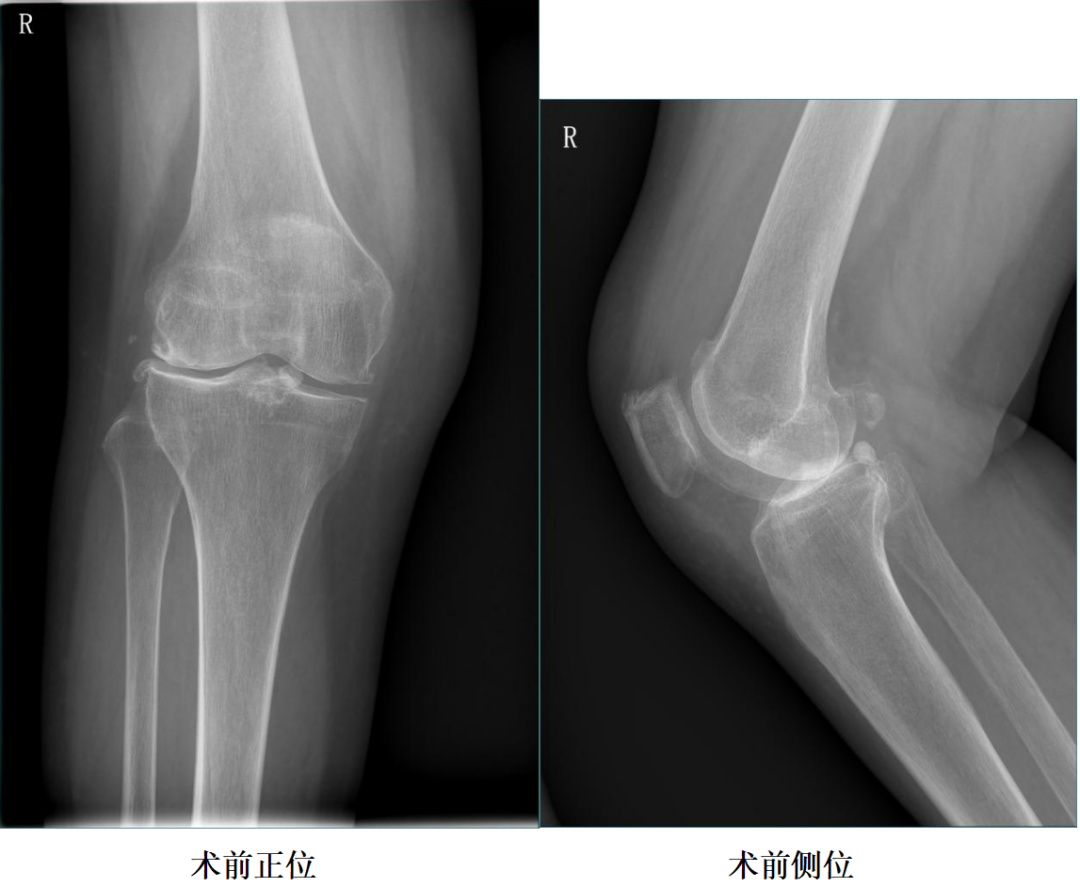

二、术前X片

X-Ray:右膝外侧间隙明显狭窄,站立位外侧间隙消失,内侧间隙正常,膝关节稳定。